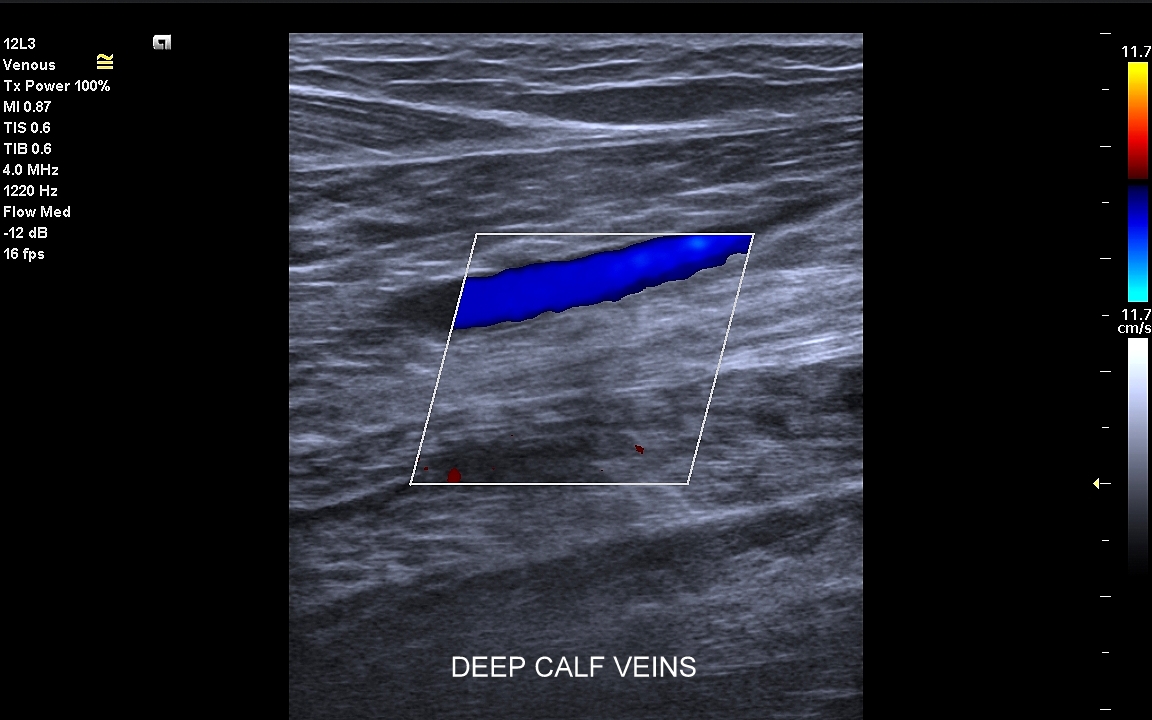

Żyły kończyn dolnych. W obrębie żył kończyn dolnych znajdują się dwa zasadnicze układy żylne – układ żył głębokich i układ żył powierzchownych. Oba układy łączą się razem bezpośrednio w okolicy pachwiny oraz dołu podkolanowego; poza tym na różnych poziomach kończyny przy pomocy żył przeszywających. Każde połączenie układu głębokiego i powierzchownego posiada naturalnie zastawkę, która zapobiega cofaniu się krwi w niewłaściwym kierunku. Prawidłowym kierunkiem jest przepływ z układu powierzchownego do głębokiego oraz ku sercu. Zarówno w układzie powierzchownym, jak i głębokim lokalizować mogą się poważne choroby takie jak zakrzepica, czy niewydolność żylna.

Czym jest zakrzepica żył? Zakrzepica żylna polega na powstaniu skrzepu wewnątrz naczynia żylnego i wtórnym rozwoju stanu zapalnego w okolicy naczynia. Choroba dotyczyć może układu powierzchownego żył lub żylaków, a w tym wypadku nie jest zwykle stanem niebezpiecznym; a także układu głębokiego żył, co z kolei jest stanem potencjalnie zagrażającym życiu, gdyż może sprowokować zatorowość płucną. Zakrzepica żył głębokich (ang. deep venous thrombosis DVT) częściej występuje w obrębie żył kończyn dolnych, następnie w obrębie żył biodrowych, rzadziej w żyle podobojczykowej i żyłach głębokich kończyny górnej. Przyczyny zakrzepicy żylnej są różnorodne i obejmują m. in. długie podróże, długotrwałe unieruchomienie, operacje ortopedyczne, chirurgiczne i szczękowe, urazy tkanek miękkich oraz złamania kości, genetycznie uwarunkowane trombofilie, nowotwory złośliwe, odwodnienie, infekcje miejscowe i ogólnoustrojowe. W przypadku zakrzepicy żyły podobojczykowej klasyczną jej przyczyną jest ucisk; w swojej praktyce klinicznej dr Szczepański spotkał się z zakrzepicą podobojczykową wywołaną m. in. przez ciężki plecak, wyciskanie sztangi na siłowni, czy przez uprawianie wspinaczki skałkowej. W warunkach szpitalnych zakrzepica żyły podobojczykowej lub żyły szyjnej wewnętrznej może pojawić się w wyniku zakładania cewników dożylnych. Sprawne wykrycie zakrzepicy w badaniu USG, a następnie wdrożenie odpowiedniej terapii uchronić może pacjenta przed powikłaniami ostrymi (np. zator płucny), jak i opóźnionymi (np. zespół pozakrzepowy).

Badanie USG żył kończyn dolnych najczęściej wykonywane jest w ramach diagnostyki niewydolności żył powierzchownych oraz ich objawów w postaci pajączków żylnych, żylaków kończyn dolnych, obrzęków i owrzodzeń żylnych. Kolejnym pod względem częstości wskazaniem do badania Doppler żył jest podejrzenie zakrzepicy żył głębokich kończyn dolnych, monitorowanie leczenia zakrzepicy oraz ocena jej powikłań odległych. Powikłaniem nieleczonej zakrzepicy żył głębokich może być zespół pozakrzepowy manifestujący się masywnymi obrzękami kończyny i zaburzeniami troficznymi. Badanie USG Doppler żył kończyn dolnych często uzupełniane jest oceną układu żył centralnych w miednicy i jamie brzusznej. W tych obszarach również pojawiać się mogą żylne zmiany zakrzepowe, niedrożności żył, a nawet zmiany nowotworowe.

Podczas najczęściej przeprowadzanego badania, tj. USG Doppler kończyn dolnych, oceniane są żyły głębokie oraz powierzchowne na całej długości kończyny – od stóp aż do pachwiny. Czasami mogą zaistnieć wskazania do rozszerzenia badania na wyższy poziom układu żylnego, tj. na żyły biodrowe w miednicy i żyłę główną dolną w jamie brzusznej. Badanie USG żył jest badaniem dynamicznym, tzn. oprócz oceny wyglądu żył wykonuje się różnorodne próby czynnościowe, takie jak kompresja, głębokie oddychanie, próba Valsavy, podczas których rejestruje się przepływy krwi w żyłach.

Czy USG Doppler wykrywa zakrzepicę? Tak, badanie Doppler żył jest najważniejszą metodą diagnostyczną wykrywającą zakrzepicę żył głębokich i powierzchownych. W związku z faktem, iż nieleczona zakrzepica żył głębokich może być przyczyną niebezpiecznego zatoru płucnego lub utraty kończyny badanie Doppler należy wykonać jak najszybciej w każdym przypadku podejrzenia zakrzepicy.